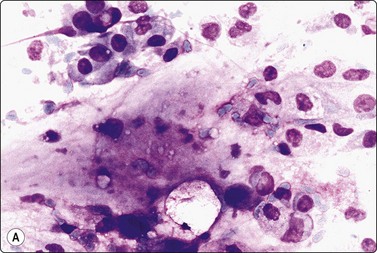

image image

Fig. 4.26 Chronic sialadenitis

(A) Sheet of ductal epithelium showing squamous metaplasia. This could be mistaken for low-grade mucoepidermoid carcinoma or other low-grade neoplasm (Pap, HP); (B) Corresponding histology, most acinar epithelium replaced by fibrous tissue with patchy inflammatory cell infiltration, and prominent ducts showing mild reactive atypia and squamous metaplasia (H&E, IP).

Most cases of chronic sialadenitis referred for FNB are in a late stage when interstitial fibrosis and atrophy of acinar tissue have taken place. The inflammatory cell infiltration may have subsided and may be sparse and patchy. FNB smears are therefore often scanty, mainly of ductal epithelial cells associated with only few acinar cells and inconspicuous inflammatory cells. Fragments of fibrous stroma are often present (Fig. 4.25). Crystalloids may be present in the aspirate.95 Regenerating ductal epithelium in chronic sialadenitis may undergo squamous metaplasia and may appear atypical (Fig. 4.26). Mucus-like material from dilated ducts may be present. This may be suggestive of a neoplastic lesion or even of malignancy, mainly low-grade mucoepidermoid tumor. Multiple sampling and clinical correlation usually solves the problem.